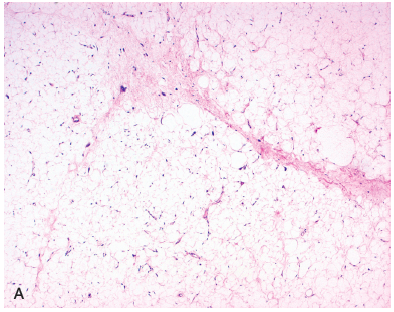

What is the morphology of the well-differentiated type of liposarcoma?

Contains adipocytes with scattered atypical spindle cells